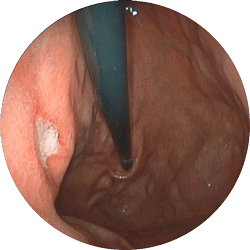

胃潰瘍

食欲不振で来院

内服薬1ヶ月で治癒